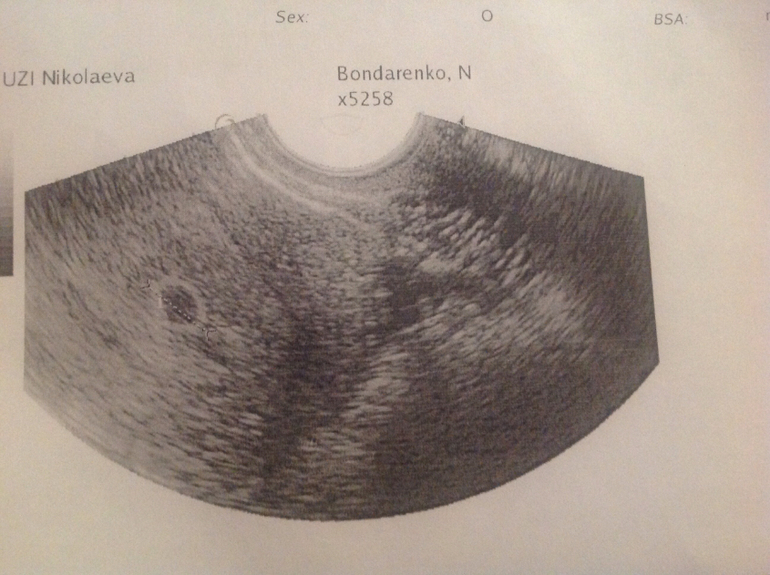

Так вот пошла я сегодня на другое УЗИ! Тоже частное, но там все врачи хорошие и милые! Они и плод увидели, и сердце слышали! И сразу сказали как аппарат засунули, что беременность маточная! Срок поставили 6,5 недель акушерских! Плоду 5,3недель. По хгч 4 недели! Но я высчитывала овуляцию и она была 17 декабря. Так что нам 4 недели и несколько дней! Я теперь спокойна, а то вчера в Oxford medical мне сказали, что это всего лишь точка..... Вот вам фото! И на такую "точку" мне сказали, что это всего лишь намек!

Про точку они наверное сказали про эмбриончик, тут его и не разглядеть! А на снимке ПЯ!) Главное, что вас нашли и все хорошо! Растите здоровенькими!